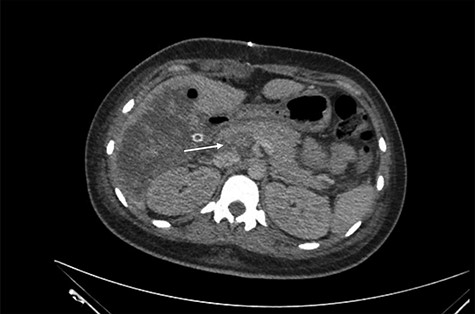

She was referred to our center on postoperative Day 4 due to progressive jaundice and encephalopathy. A triphasic contrast-enhanced abdominal computed tomography (CT) was done revealing a right liver lobe infarct, absence of the right and left hepatic arteries (Fig. 1), presence of an accessory left hepatic artery from the left gastric artery (Fig. 2) and right portal vein thrombosis with extension to the main portal vein (Fig. 3).

Accessory left hepatic artery (white arrow) on the arterial phase of the triphasic contrast-enhanced abdominal CT.

Main portal vein thrombosis (white arrow) on portal phase of the triphasic contrast-enhanced abdominal CT.